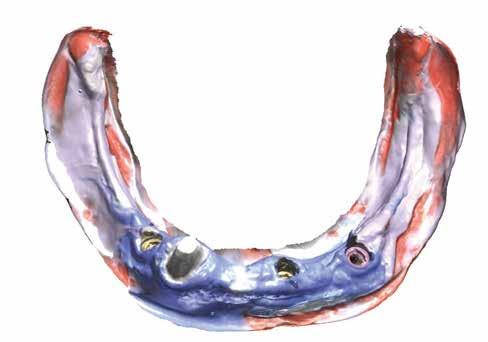

Középkorú páciens, felül négy maradék fog, alul egy szemfog (2. kép). Olyan pótlást akartunk készíteni, amelyik a maximálisan elképzelhető ideig nyújt elégedettségre okot adó komfortot. Ehhez mi a teleszkópoknak szinte utánozhatatlan alkalmazását látjuk megoldásnak. A teleszkóp szilárd,

2. kép: Megtartandó maradékfogazat.

lak használata, hogy precízen felmérhető legyen a preparációs határ (5. kép). Az optikai beolvasás miatt a kezelőcsapat tudatában kell legyen annak, hogy a nyálkahártya rezilienciája nem lesz figyelembe véve. Ezt a fontos információt a későbbiekben, a mock-up készítése során kell rögzíteni. Általánosságban kijelenthető, hogy a felső állcsont optikai beolvasása problémamentesebb, mint az állkapocsé. A bemutatott esetben különösen az erősen sorvadt gerinc és a szublingvális szájfenék jelentett kihívást, hiszen minél több alsó állcsontot kellett lemintázni. A cara i700-sal a felhasználó lehetőséget kap kiegészítő információként az ideiglenes pótlás bazális felszínének beolvasására, és ennek öszszevetésére a szájképletekkel. Csak ezen az úton lehetséges akceptálható lenyomatot készíteni (6–8. képek).

7. kép: Az alsó állcsont a becsavarozott digitális lenyomatvételi fejekkel.

8. kép: Az ideiglenes bazális részének összehasonlításával a szájfenék könnyebben meghatározható.